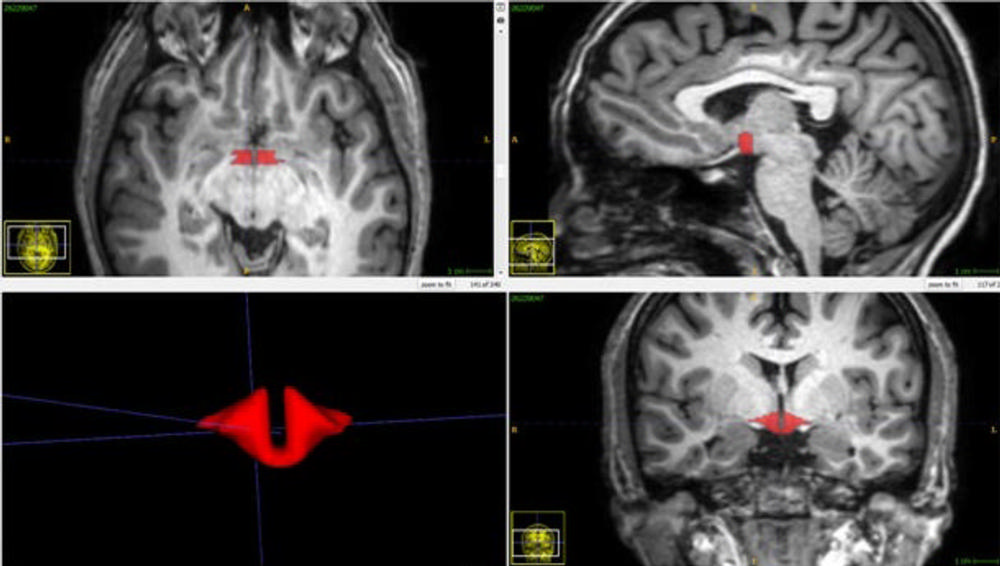

Structural effects of sex hormones, including oral contraceptive pills, on the human hypothalamus have never been reported, according to the researchers. This may be in part because validated methods to quantitatively analyze MRI exams of the hypothalamus have not been available.

In his study, Dr. Lipton and colleagues recruited a group of 50 healthy women, including 21 women who were taking oral contraceptives. All 50 women underwent brain MRI, and a validated approach was used to measure hypothalamic volume.

Video 2. The Human Hypothalamus: MRI-based Segmentation & 3D Rendering

Download

Figure 7. Brain MRI depicting hypothalamus in red.

High-res (TIF) version